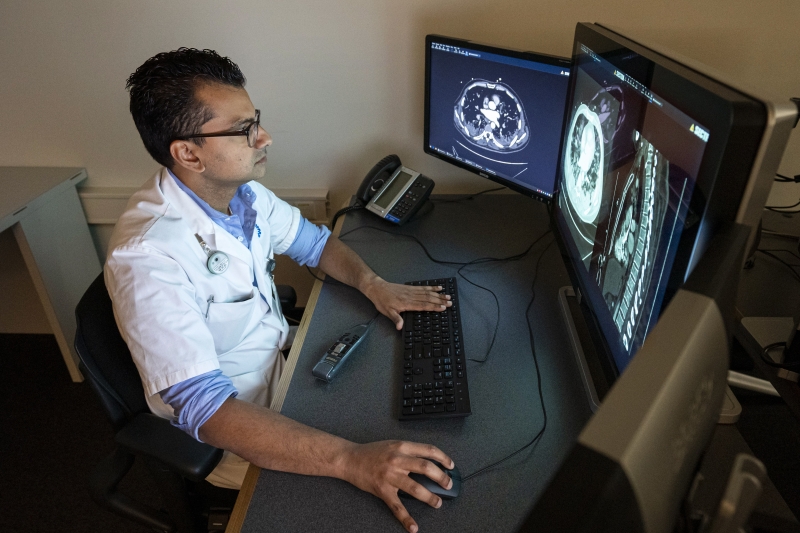

Radiologist Firdaus Mohamed Hoesein studies CT scans of COVID-19 patients. Photo: Thijs Rooimans

CT scans, which are part of standard care, will be analyzed using the latest artificial intelligence methods. Thirona will contribute by analyzing chest CT scans of participants for abnormalities with its CAD4COVID and LungQ software solutions.